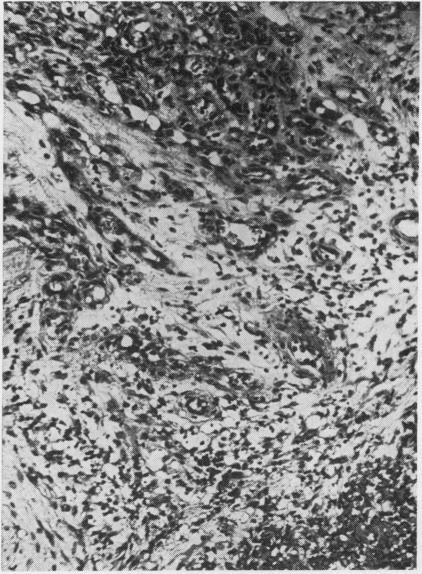

A comparison has been made between two vasoformative lesions, Kaposi's sarcoma and granuloma pyogenicum, as they are encountered in Uganda. Both are predominantly skin lesions arising in the distal extremities, may resemble each other clinically, and are widespread in their distribution in Ugandan communities. They bear a reciprocal relationship to each other as regards age and sex incidence, Kaposi's sarcoma being mainly a disease of adult males and granuloma pyogenicum a disease of immature males and females. Histologically there are many similarities between them, the essential difference being the presence of a spindle-cell sarcomatous element in Kaposi's sarcoma. The clinical behaviour reflects this difference in that granuloma pyogenicum develops quickly and appears to be self-limiting, while Kaposi's sarcoma is slowly progressive and shows much less tendency to regress. On the basis of these findings it is concluded that, although these two lesions may be completely unrelated, it is possible that both represent a response of the vasoformative elements in the skin to a similar form of initiating stimulus and that hormonal or sex-linked genetic factors determine which lesion will develop in response to this stimulus. The presence of intracytoplasmic inclusion in the tumour cells of Kaposi's sarcoma might be of significance in the histogenesis of this tumour, and of value in its histological differentiation from granuloma pyogenicum.

对乌干达出现的两种血管形成性病变——卡波西肉瘤和脓性肉芽肿进行了比较。两者主要都是发生在四肢远端的皮肤病变,在临床上可能彼此相似,并且在乌干达社区中分布广泛。它们在年龄和性别发病率方面呈反比关系,卡波西肉瘤主要是成年男性的疾病,而脓性肉芽肿是未成年男性和女性的疾病。组织学上它们有许多相似之处,本质区别在于卡波西肉瘤中存在梭形细胞肉瘤成分。临床行为反映了这种差异,脓性肉芽肿发展迅速且似乎有自限性,而卡波西肉瘤进展缓慢且消退倾向小得多。基于这些发现得出结论,尽管这两种病变可能完全无关,但两者都有可能代表皮肤血管形成成分对类似形式的起始刺激的反应,并且激素或性连锁遗传因素决定了对这种刺激会产生哪种病变。卡波西肉瘤肿瘤细胞中胞质内包涵体的存在可能对该肿瘤的组织发生具有重要意义,并且在其与脓性肉芽肿的组织学鉴别中具有价值。